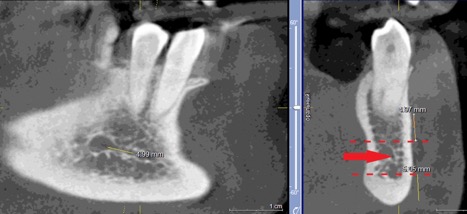

При измерении расстояния от резцовой петли до вестибулярной стенки нижней челюсти и её топографии в области правила «трёх пятёрок», выделено три положения канала, в котором проходит резцовая петля: канал прилежит, т.е. стенка канала образована кортикальной частью (рис 3), касается, т.е. имеет одну общую точку (рис 4) и не имеет общих точек.

Рисунок 3. КЛКТ Сагиттальный и коронарный реформаты переднего отдела нижней челюсти.

Стенка канала образована кортикальной частью кости.

Красная стрелка – «резцовая петля».

Красный пунктир – канал проходит в проекции участка правила «трёх пятёрок».